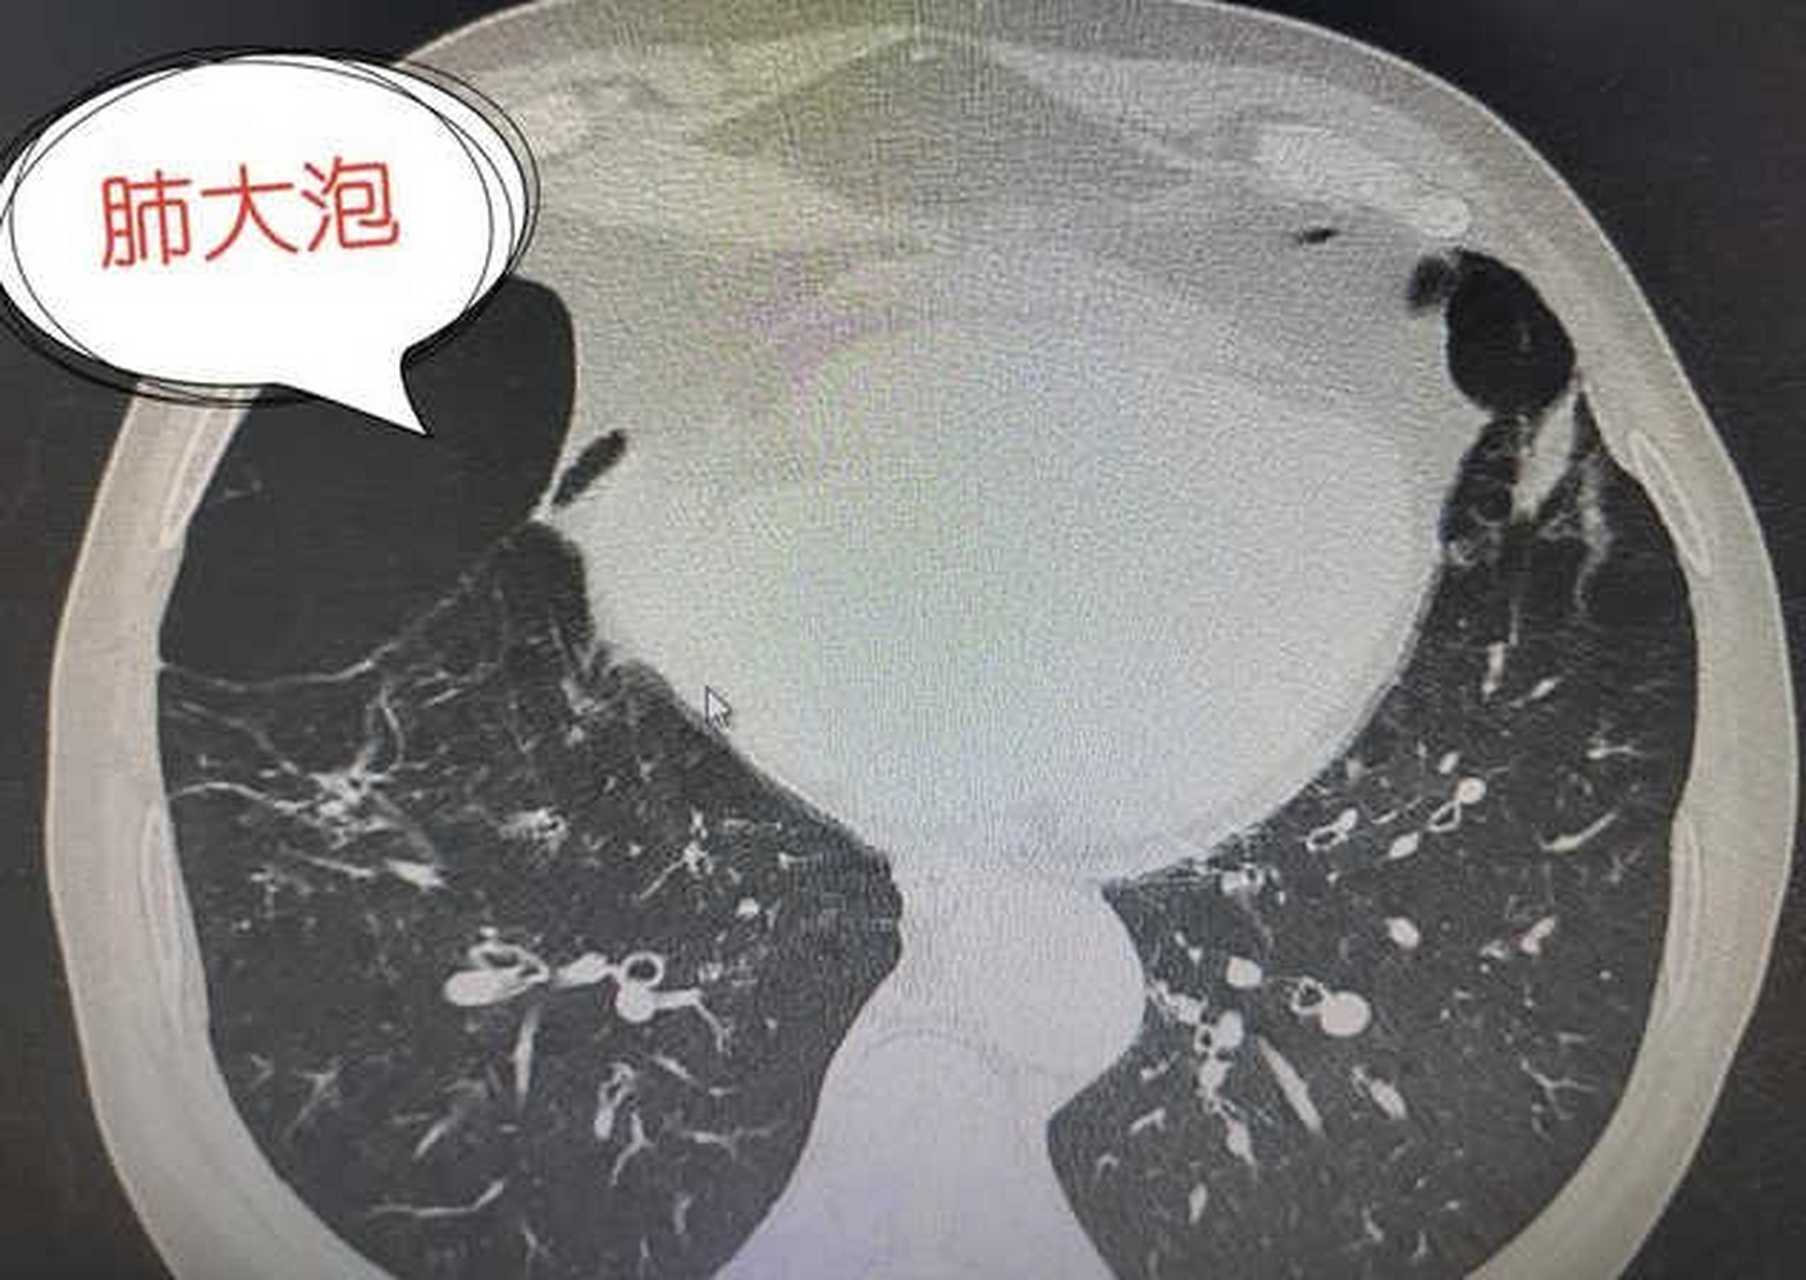

怎么做才能让肺大泡不增大呢?

一般来说,肺大泡一旦形成,它是不会自己恢复的,我们只能防范,保护

肺大泡影响肺功能,有些人需要终生用药,能做手术把它切除吗?

肺大泡究竟是怎么回事?